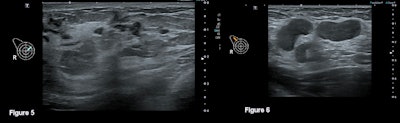

An expected predominant use of ultrasound was observed, with a total of 3,011 ultrasound exams carried out (98.7% of all scans) over the four-year period.

A total of 570 patients received an ultrasound Royal College of Radiologists (RCR) breast score of R3 and above and thus proceeded to biopsy, representing 10% of all patients who underwent imaging over the four-year period. A 63.7% increase in the number of biopsies required was seen from 2018 (n = 113) to 2021 (n = 185).

The average age at diagnosis over the four-year period was 31.8, and 18 of the 36 patients diagnosed with cancer from 2018-2021 were referred with a "likely benign" clinical examination indicated by an E3 score. The average size of tumor mass seen on ultrasound per year was 33.4 mm in 2018, 46 mm in 2019, 40.2 mm in 2020, and 49.86 mm in 2021.